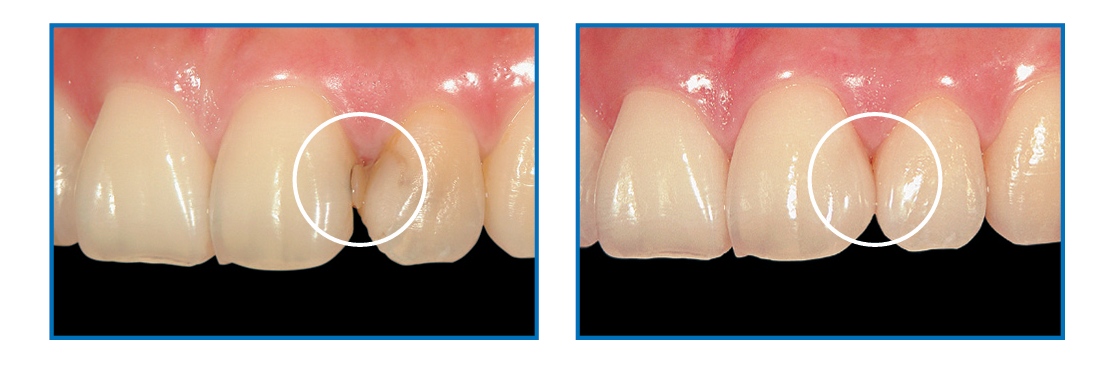

Aesthetic Outcomes:

- Extremely low film thickness (5µm).

- Eliminates marginal stain lines.

Aesthetic Benefits and Ease of Use

- Emphasizes aesthetic outcomes with reduced marginal staining.